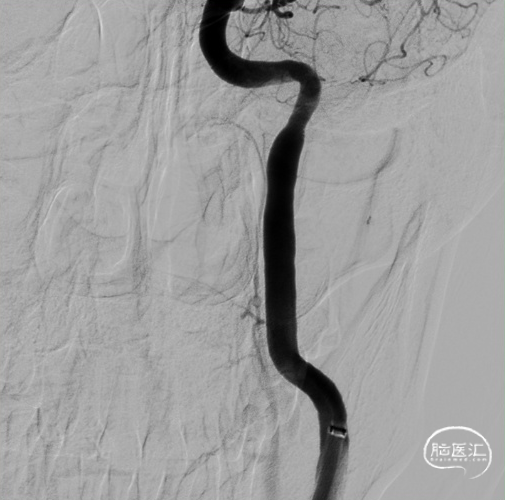

急诊DSA:

左侧颈内动脉C3段附壁血栓形成,左侧大脑中动脉M2段上干分支串联闭塞。

左侧大脑中动脉上干M2、下干M5段多发栓塞。

左侧椎动脉无向左侧大脑半球代偿供血。

前交通未见开放,未向左侧大脑半球代偿供血。

单弯导管、泥鳅导丝引导8F天梯高性能长鞘进入颈内动脉。

置入心玮吞川088颅内血栓抽吸导管到颈升段。

置入6.0*35mm 取栓支架远端保护。

取栓支架到位后,造影示血栓无逃逸。

支架保护下予心玮吞川088颅内血栓抽吸导管行栓子抽吸。

血栓影减少一半。

再来一把SWIM取栓。

血栓影大部分清除。

远端血管灌注改善,mTICI 2c。